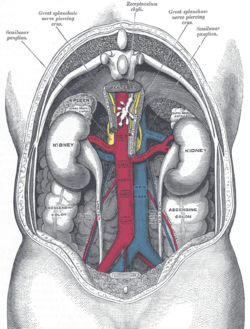

The abdominal aorta and its branches (internal spermatic vessels labeled at right) | |

They are two slender vessels of considerable length, and arise from the front of the aorta a little below the renal arteries.

Each passes obliquely downward and lateralward behind the peritoneum, resting on the Psoas major, the right lying in front of the inferior vena cava and behind the middle colic and ileocolic arteries and the terminal part of the ileum, the left behind the left colic and sigmoid arteries and the iliac colon.

Each crosses obliquely over the ureter and the lower part of the external iliac artery to reach the abdominal inguinal ring, through which it passes, and accompanies the other constituents of the spermatic cord along the inguinal canal to the scrotum, where it becomes tortuous, and divides into several branches.